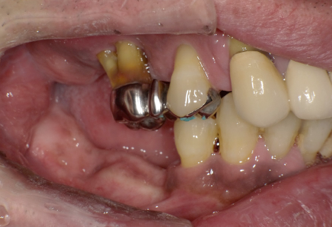

術直後の写真です

オールオン6本のインプラントをいれました

初期固定もよかったので即時荷重をおこなっています

術後2週間 傷もきれいに治ってきています